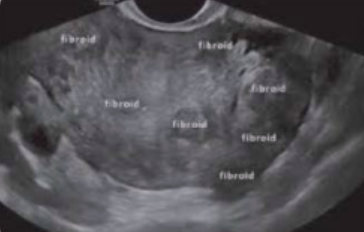

What type of fibroid is depicted in this image?

A. Intramural

B. Submucosal

C. Subserosal

D. Pedunculated

Subserosal